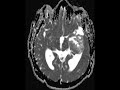

Epidermoid

There is a heterogeneous T1 hypointense, T2 hyperintense, non-enhancing lesion which demonstrates restricted diffusion centered in the left middle cranial fossa with adjacent post-surgical changes and extension into the temporal horn of the left lateral ventricle and the left lateral aspect of the suprasellar and prepontine cisterns. The mass incompletely suppresses on T2 FLAIR. Signal characteristics are classic for an epidermoid. Most epidermoids are intradural and commonly involve the basilar cisterns. They tend to follow the signal of CSF, but do not completely suppress on FLAIR. Diffusion restriction is the defining imaging feature. Treatment is with surgical resection.